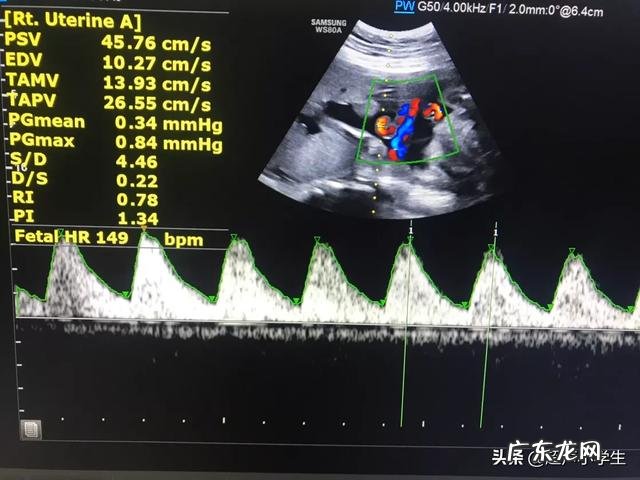

1、胎心率的正常值——110~160次/分钟

如果胎心率连续10分钟过高或是过低,都说明胎儿在宫内出现问题 。

1)胎龄

胎心率随胎龄的不同而不同 。

早在孕5~6周,胚胎出现原始心管搏动,这时宝宝的心率和妈妈的心率差不多,80~85次/分钟;

到孕9周左右,胎心率加快到170~200次/分钟;

到了怀孕中期,胎心率又会逐渐放慢,会稳定在120~160次/分钟;

到孕晚期,胎心率会略微下降,约为110~150次/分钟 。

统计显示,怀孕前5个月平均胎心率为162次/分钟,5~7.5月平均147次/分钟,7.5~10月平均139次/分钟 。

2)胎动

? 胎儿清醒时比睡觉时胎心率高;

? 胎动后胎心率会增高 。

3)胎儿缺氧

胎儿宫内缺氧会导致胎心持续过高、持续过低或者胎心率平直起伏波动不好 。

4)孕妈妈的身体状况

?孕妈妈情绪过于激动、焦虑,会是胎心率增高;

?孕妈妈的某些疾病,比如发烧或是甲亢,会使胎心率升高;

?孕妈妈服用的某些药物,也会使胎心率发生变化,比如保胎药可能会使胎心率升高,治疗心率失调的药可能会使胎心率降低 。